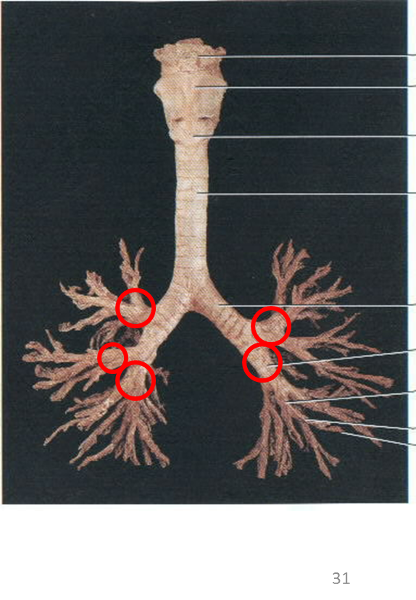

Bronchioles

Horizontal fissure (of right lung)

Left/right oblique fissue (of lung)

Left/right primary bronchus/bronchi

Secondary bronchi

Upper/middle/lower lobe (of lung)